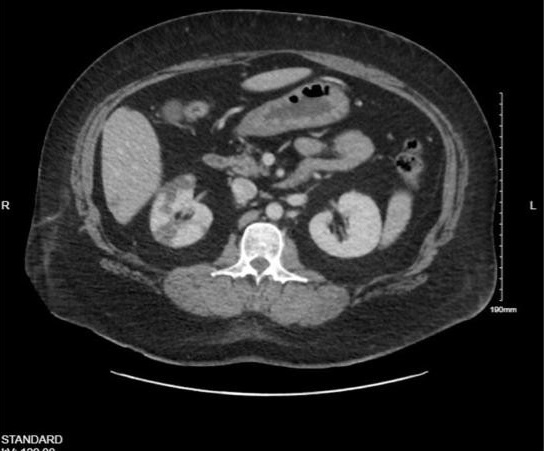

A 46-year-old nonsmoking woman with a medical history of hypertension, hyperlipidemia, type I diabetes, and duodenal cancer with a BRCA gene mutation underwent bilateral skin-sparing mastectomies and immediate deep inferior epigastric perforator (DIEP) flap reconstruction. She received preoperative subcutaneous heparin and intraoperative heparinized saline flushes. On postoperative day 10, she presented with chest pressure, nausea, and vomiting. Computed tomography imaging revealed a right renal infarct (Figure 1). Exam findings included blanching erythema and large blisters over the DIEP flaps (Figure 2). Surgical reexploration confirmed patent DIEP pedicles with presumed bilateral intraflap microthrombosis compromising skin paddle perfusion. Following administration of intravenous (IV) heparin, the patient developed severe vasodilatory shock and cardiac arrest requiring cardiopulmonary resuscitation. There was a return of spontaneous circulation after administration of epinephrine, suggesting an anaphylactic reaction. She was diagnosed with heparin-induced thrombocytopenia (HIT) based on a positive platelet factor 4 (PF4) antibody and serotonin release assay. She was transitioned to argatroban and later discharged on apixaban. The patient ultimately experienced partial flap loss but recovered well. The flaps successfully integrated, and no further issues were encountered in the long term.

Figure 1. Computed tomography scan of the abdomen depicting the patient’s right renal infarct on readmission (postoperative day 10).